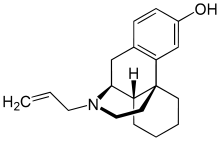

Morphinans

Morphinan series

- 3-Hydroxymorphinan

- 4-Chlorophenylpyridomorphinan

- Cyclorphan

- Levargorphan

- Levorphanol

- Levophenacylmorphan

- Levomethorphan

- Methorphan (racemethorphan)

- Morphanol (racemorphanol)

- Norlevorphanol

- N-Methylmorphinan

- Oxilorphan

- Phenomorphan

- Proxorphan

- Ro4-1539

- Stephodeline Xorphanol

Structures

| Other morphinans | ||||

|---|---|---|---|---|

4-chlorophenylpyridomorphinan 4-chlorophenylpyridomorphinan |

Cyclorphan Cyclorphan |

Dextrallorphan Dextrallorphan |

Levargorphan Levargorphan |

Levophenacylmorphan Levophenacylmorphan |

Levomethorphan Levomethorphan |

Norlevorphanol Norlevorphanol |

N-Methylmorphinan N-Methylmorphinan |

Oxilorphan Oxilorphan |

Phenomorphan Phenomorphan |

Dextromethorphan Dextromethorphan  levomethorphan levomethorphan |

Morphanol Morphanol |

Ro4-1539 Ro4-1539 |

Stephodeline Stephodeline |

Xorphanol Xorphanol |